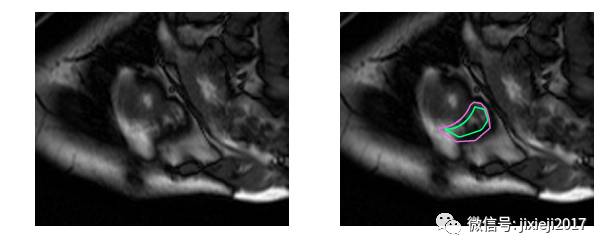

不使用医学术语,识别右心室困难的原因是:左心室是一个厚壁的圆柱型区域,而右心室是一个不规则形状的物体,较薄的心室壁有时会与周围的组织混在一起。下图是MRI快照中手工绘制的右心室内壁和外壁(心内膜和心外膜)轮廓:

上图的分割较简单。下面是一个比较困难的分割: